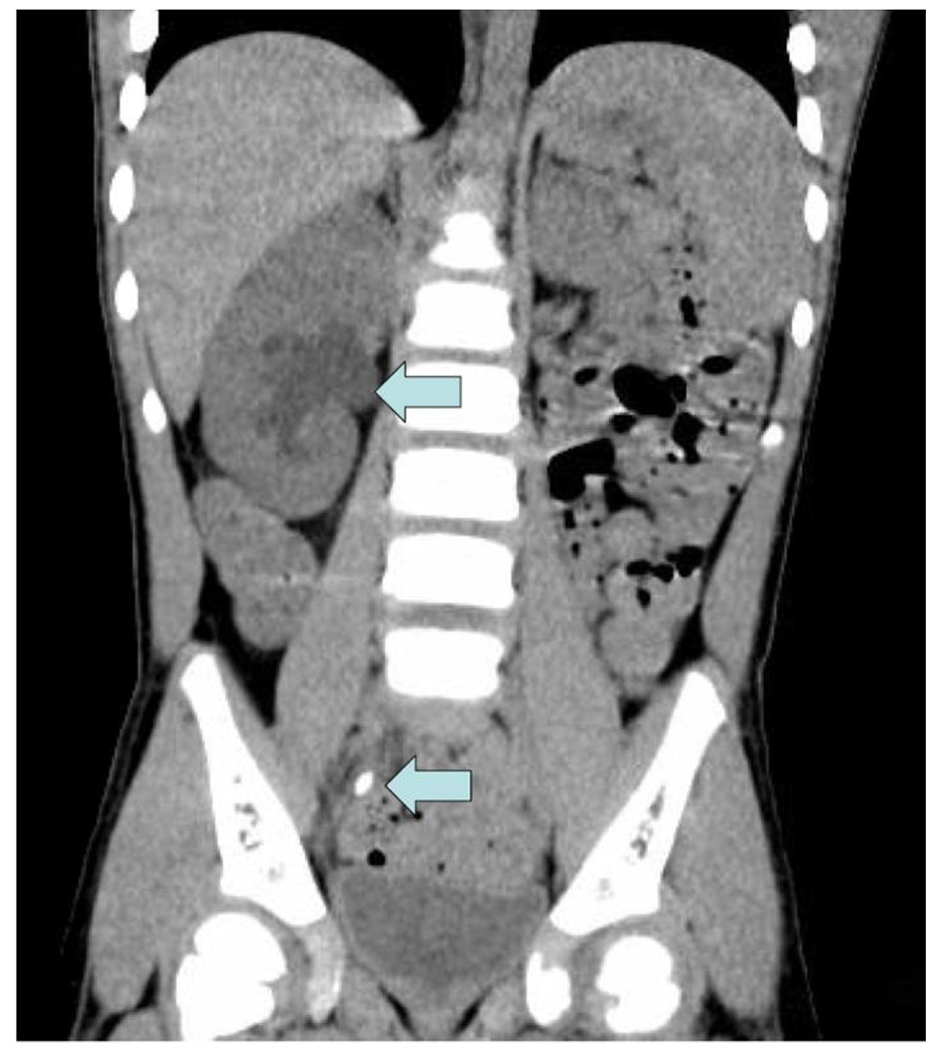

A 3-year-old boy previously diagnosed with Lesch-Nyhan disease presented with abdominal pain, nausea, and vomiting in September 2014. He had a similar presentation to the hospital 3 months prior and was noted to have right hydroureteronephrosis on renal sonogram at that time, which persisted on repeat sonogram. No urolithiasis was noted on sonogram. He underwent an abdominal/pelvic CT scan which revealed an obstructing stone in his right ureter of 7 mm (Fig. 1) and a large left renal pelvis stone of about 1 cm (Fig. 2). His renal function was elevated with a Cr of 0.7 mg/dL (0.4 - 0.7 mg/dL) and his eGFR was 59.9 mL/min/1.73 m2 calculated using the Schwarz equation. He was currently on treatment with allopurinol and his serum uric acid was 3.7 mg/dL (2.1 - 5.6 mg/dL) and his urinary uric acid level was 8.8 mg/dL (9.0 - 114 mg/dL). Urine pH was 7.0. The patient underwent cystourethroscopy and bilateral lithotripsy along with bilateral ureteral stent placement. Stone analysis revealed 100% xanthine stones. The patient was discharged and sent home from this encounter but has since presented twice with obstructing xanthine stones that have required intervention over the past several years.

![]() Click for large image | Figure 1. Right hydronephrosis and obstructing ureteral stone. |